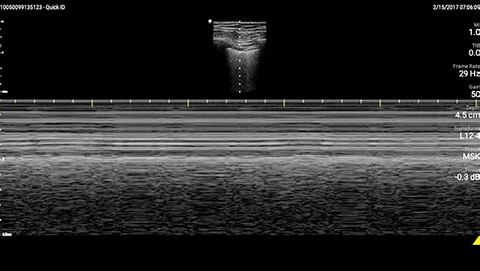

The patient had reduced LV systolic function without new or severe valvular pathology, a dilated, non-collapsing IVC, and diffuse B lines (left greater than right) on lung ultrasound imaging.

M-mode demonstrating lung sliding

A 69 year-old male with a known history of hypertension, chronic non-oliguric kidney disease, insulin dependent diabetes, and chronic systolic heart failure with an ejection fraction (EF) of 25% secondary to ischemic cardiomyopathy was recovering in the CardioVascular ICU after four vessel coronary artery bypass grafting. His post-operative course had been complicated by acute respiratory failure, acute on chronic non-oliguric renal failure, delirium and pseudomonas pneumonia. The patient’s oxygenation had been improving on antibiotic therapy with aggressive diuresis and ionotropic support, although his BUN and creatinine remained quite elevated. Family had been reluctant to initiate dialysis given his clinical improvement and ability to make urine with diuretic support. The patient was extubated to high-flow oxygen by nasal cannula after successfully passing a spontaneous breathing trial, although, he had failed extubation one week prior secondary to acute dyspnea and hypoxia. Two days later, the patient began to have a fever, worsening shortness of breath with increased oxygen requirements, and inability to wean ionotropic and vasopressor support further. Because of concern for septic shock, the patient was given a total of 500ml of crystalloid overnight. Whole blood lactic acid levels returned at 1.6, serum creatinine increased from 5.8 to 6.11, and the patient’s fever and shortness of breath worsened. Repeat cultures were obtained and antibiotic therapy was broadened further while initiating non-invasive positive pressure ventilation for acute respiratory distress. In the interim, while awaiting laboratory results and chest X-ray imaging, POCUS with a three-point exam (F-TTE, IVC collapsibility, and lung ultrasound) was used for bedside evaluation of the etiology of the patient’s dyspnea. Within minutes, and with the additive information from the combined cardiac, subcostal IVC, and lung ultrasound imaging, the patient was diagnosed with acute on chronic congestive heart failure and flash pulmonary edema as the cause of his respiratory distress and hypoxia.